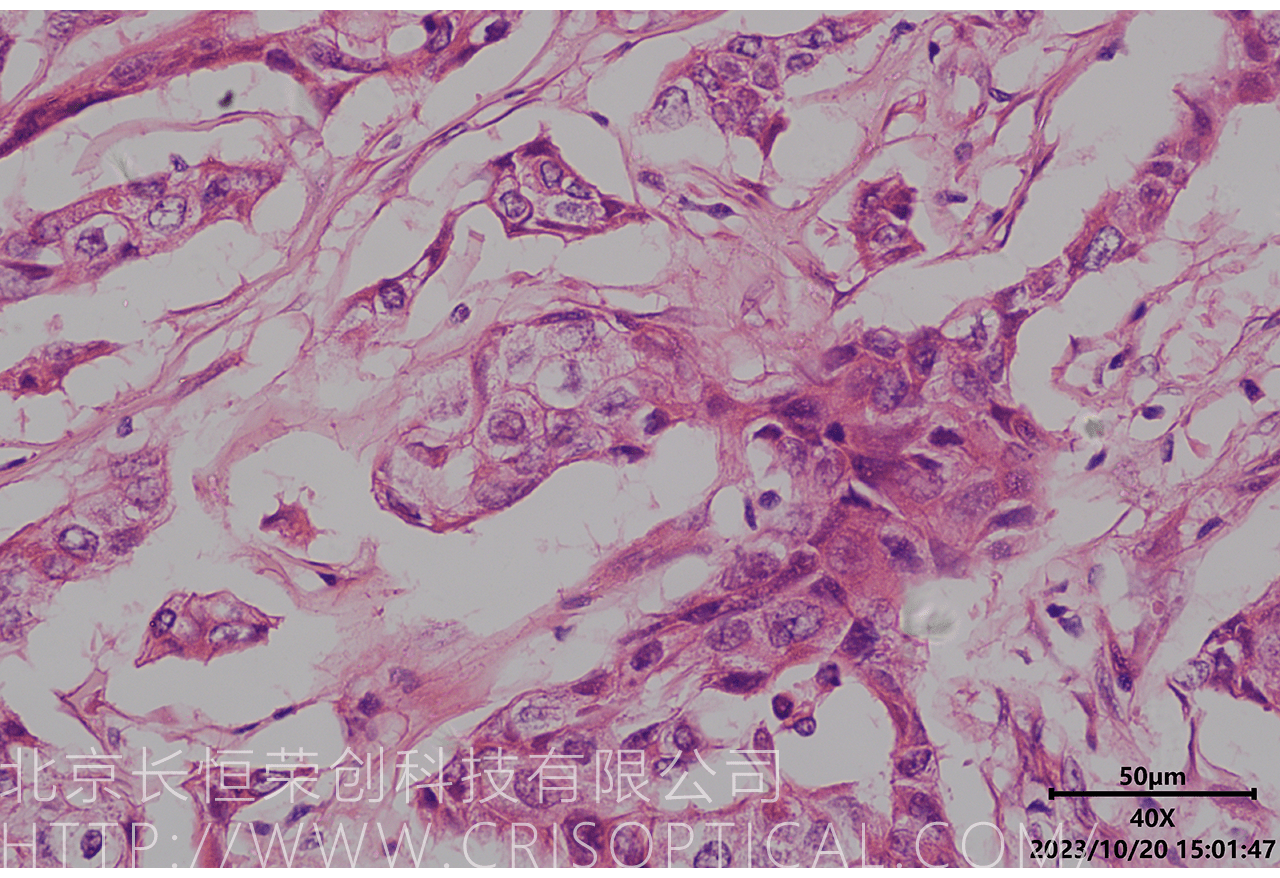

腫瘤診斷:對癌癥和其他腫瘤的病理切片觀察是確定腫瘤類型、分級和分期的關鍵步驟。醫(yī)生通過觀察組織樣本中的細胞形態(tài)、核形狀、分裂活性和其他特征,可以識別腫瘤的類型,幫助決定治療方法。